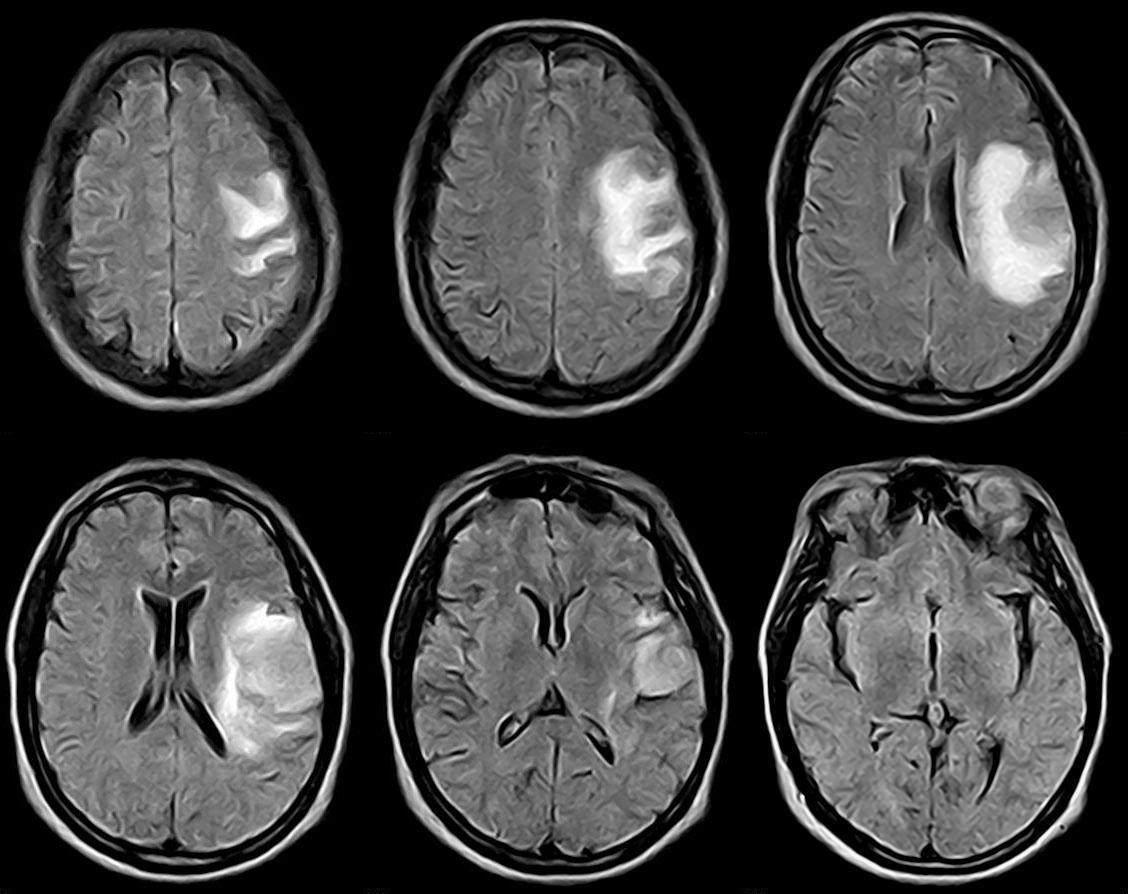

(1)CT或是MRI检查

现在的常规检查包括 CT和 MRI。由于不同肿瘤的发生发展,其影像学表现也有所不同。脑平片能显示颅内高压、肿瘤钙化和松果体钙化移位。脑室造影可以显示脑血管的移位及肿瘤血管。但是通常用 CT和 MRI来代替。